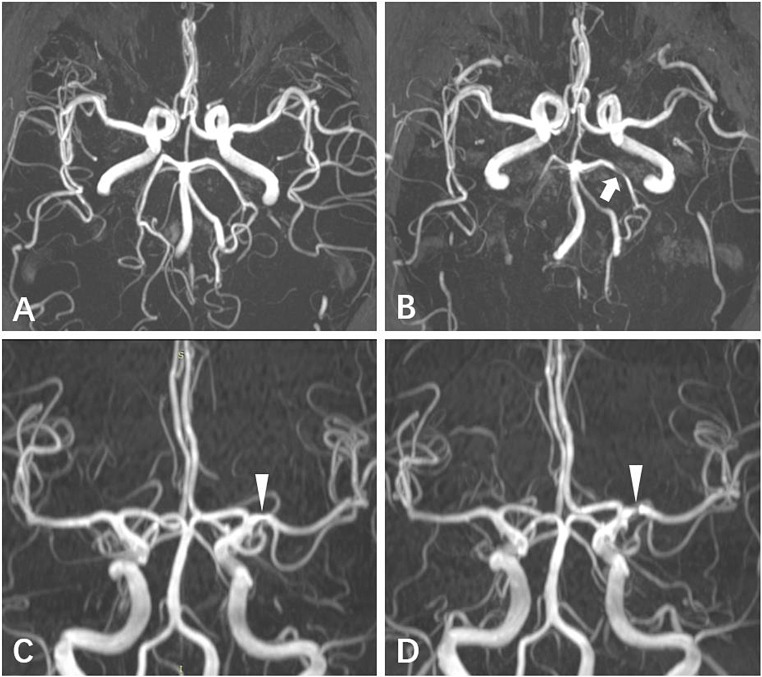

Incident lacunes and CMB were defined as one or more new lesions observed during follow-up imaging. WMH progression was described as the annualized volume change ([follow-up WMH volume − baseline WMH volume]/follow-up duration). Incident ICAS was defined as new stenosis occurring in at least one artery or an increase in the severity of the original arterial stenosis compared to that at baseline. Figure 2 showed illumination of incident ICAS. Trained physicians who were blinded to all clinical data independently evaluated the ICAS, lacunes, and CMB. Intra-rater agreements have been described elsewhere [10].

Fig. 2.

Illumination of incident intracranial artery stenosis (ICAS). Figure 2A shows a participant without ICAS at baseline and Fig. 2B shows incident stenosis in the bilateral posterior cerebral arteries at follow-up (arrow). Figure 2C shows a participant with stenosis in the left middle cerebral artery at baseline, while Fig. 2D shows worsened stenosis in the left middle cerebral artery at follow-up (arrowhead)